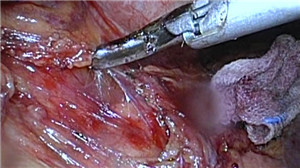

腹腔镜下右侧前入路根治性近端胃大部切除术(双通道+Overlap消化道重建)